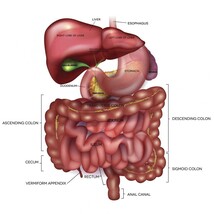

BLACK SEED OIL LIVER BOOSTER: The liver is one of the most important organs in the body. Nearly every toxin gets processed through the liver, and the bile from the liver is the key to digesting fats and keeping your mind and body happy and healthy. For those that have struggled with poor liver function due to man made side effects or alcohol consumption black seed oil could greatly speed the healing process. In a recent animal model study, scientists discovered that black seed oil benefits the function of the liver and may help prevent both damage and disease.